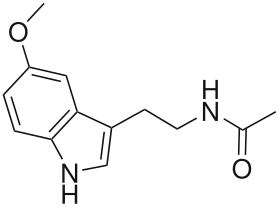

Melatonin

Synthesis

Pinealocytes synthesize the hormone melatonin by first converting the amino acid tryptophan to serotonin. The serotonin is then acetylated by the AANAT enzyme and converted into N-acetylserotonin. N-acetylserotonin is converted into melatonin by the enzyme hydroxyindole O-methyltransferase (HIOMT), also known as acetylserotonin O-methyltransferase (ASMT).[1] Activity of these enzymes is high during the night and regulated by the mechanisms previously discussed involving norepinephrine.[1]